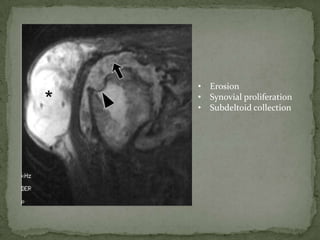

• Erosion

• Synovial proliferation

• Subdeltoid collection